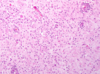

What type of cells are seen and what are their function?

Gitter cells (foamy cytoplasm)

Function: microglia that ingest myelin debris